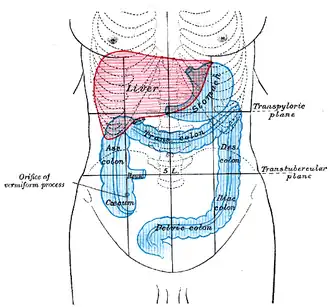

Проекция в теле человека |

Толстая кишка располагается в брюшной полости и в полости малого таза, её длина колеблется от 1,5 до 2 м.

Участок толстой кишки выше слепой опоясывает брюшную полость и поэтому называется ободочной кишкой, диаметр которой 6—6,5 см и длина до 1,5 м. Начинается она со сфинктера подвздошной и слепой кишки, обеспечивающего продвижение остатков пищи в одном направлении.

Начальный участок ободочной кишки называется восходящей ободочной кишкой, следующий — поперечной, дальнейший — нисходящей. Вся ободочная кишка крепится к тыльной части брюшины при помощи брыжейки, или двойной брюшинной складки, содержащей кровеносные сосуды.